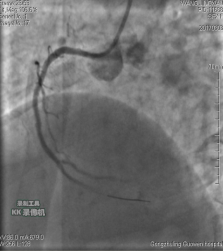

中日聯(lián)誼閆明洲教授向家屬交代病情及介入相關(guān)并發(fā)癥后,患者及家屬同意冠脈支架治療,過程順利,于右冠脈中段植入Firebird2 2.5*33mm 藥物洗脫支架1枚。

術(shù)前 術(shù)后

患者冠脈支架植入術(shù)后,胸骨后疼痛癥狀明顯好轉(zhuǎn),復查心電圖抬高的ST段回降。